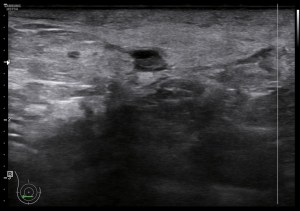

El paciente viene por un bulto en la parte derecha de la espalda, en la región paradorsal alta. Con una sonda de alta frecuencia accedo a la región, que era palpable. Lo primero que observo es que la transmisión del paciente no es buena, esto que a veces pasa que encuentras pacientes, que no sé explicar el motivo, no transmiten bien.

Me da para observar que en la zona de palpación encuentro, profundo en la imagen, un formación hiperecogénica, que está dentro de un músculo. Antes de detallar los hallazgos de la imagen lo que quise fue reconocer bien la anatomía. La piel y el tejido celular subcutánea era muy fácil, también saber que esta anatomía superficial estaba intacta y que la lesión estaba intramuscular, pero me encontraba dos planos musculares, uno superficial, el otro profundo, el profundo con la lesión.

El protocolo es el típico, cortes en eje corto y largo, con doppler, para comprobar vascularización, como línea roja del lipoma. Imágenes 3,4 y 6.

La lesión era ovalada, hiperecogénica, ocupaba gran parte del músculo, pero respetaba parte de este, que era hipoecogénico (imagen 5), recuerda que así es por definición y que ésta ecogenicidad del músculo es referencia para el resto de ecogenicidades del aparato locomotor. Como te he contado, no había doppler color ni en modo angio.